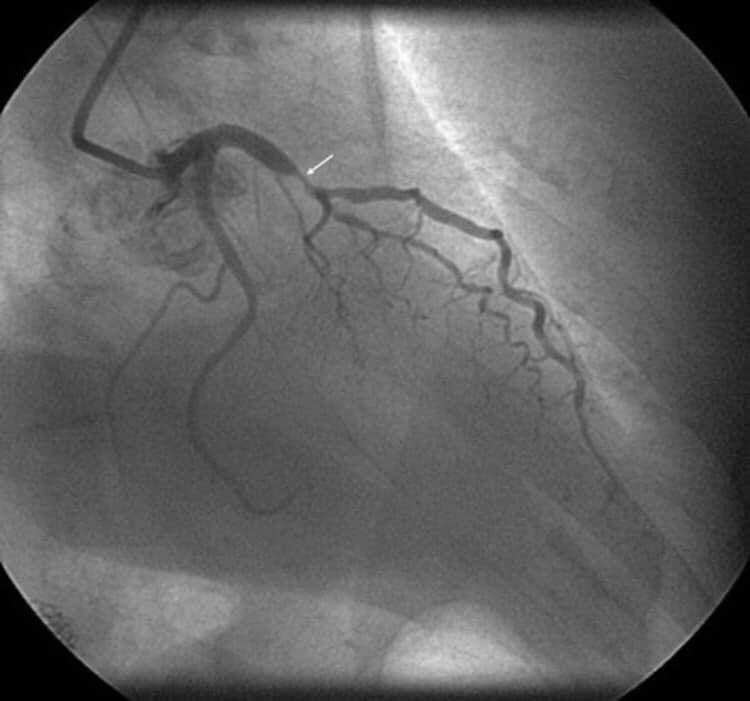

١- الألم الصدري عند الجهد او ما يعرف بالخناق الصدري المستقر على الإجهاد وهو الم يصيب المريض عند القيام بمجهود جسدي معين كمشي حوالي مئتي متر مثلا او صعود ثلاث طوابق او حمل ثقل معين. ويكون هذا الألم بشكل الم في اعلى الصدر والعنق والفك واحيانا في البلعوم والرقبة والكتف الأيسر ويمتد احيانا حتى الذراع الأيسر . وستمر هذا الالم لمدة ٣ او ٤ دقائق على ان يزول نهائيا بعد ذلك . ويحصل كل مرة على ذات مستوى الإجهاد ويتنهي مع توقف الإجهاد ليعود ويظهر مع مع معاودة الجهد ولذات المسافة او الجهد الذي قام به المريض ولذلك نقول عنه انه مستقر لأنه يظهر عند القيام ب ذات الجهد . وهو غالبا ما يكون ناتج عن إنسداد شريان واحد من الشرايين التاجية للقلب ونشخصه بسهولة عبر الوصف والفحص السريري وتخطيط القلب العادي EKG الذي قد يظهر بعض العلامات او عن طريق إجراء فحص الإجهاد: Stress test حيث تظهر ذات علامات الألم مع الركض السريع على سجادة فحص الجهد او على الدراجة الهوائية التي نستعملها من اجل ذلك. وعند إجراء التمييل او القسطرة Coronarograpgy يظهر ان هناك إنسداد واحد او إصابات على شريان واحد من الشرايين التاجية للقلب وعادة ما تكون هذه الإنسدات مهمة وتتراوح بين ٧٠ و ٩٠ او ٩٥ بالمئة ولكنها قطعا لا تكون إنسدادات كاملة اي مئة بالمئة . ومن الممكن في معظم الاحول علاجه بواسطة عملية التوسيع بالبالون والروسور وبعد ذلك تزول كل هذه العلامات او الأعراض ولكن المريض يجب ان يتناول بعدها بعض الادوية التي سنذكرها لاحقا. وطبعا عليه ايضا مراقبة عوامل الخطورة مثل إيقاف التدخين ومراقبة الدهنيات في الدم ومرض السكري وارتفاع الضغط وعلاج كل هذه الامراض بأدويتها المناسبة والقيام بتمارين رياضية شبه يومية او لثلاث مرات في الاسبوع.